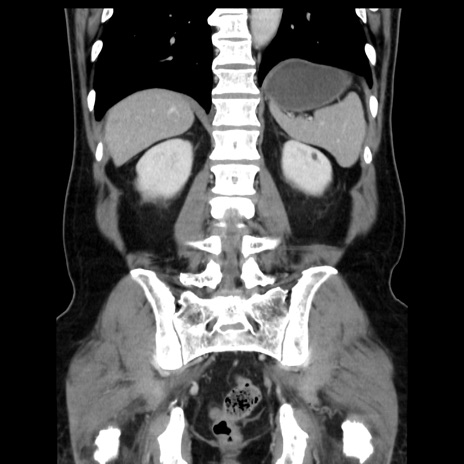

症例16(冠状断像)

【症例】 70歳代男性

【主訴】 腹痛、嘔吐

【現病歴】 約1ヶ月前より間欠的に腹痛と嘔吐あり、当院消化器内科を受診したところCTで多発する肝臓のLDAを指摘され、精査中であった。以降は消化器症状は安定していたが、2日前より嘔気と腹痛があり、同日より排便・排ガスが消失した。改善認めず、 本日、救急外来を受診した。

【既往歴】 大腸ポリープ切除後。

【身体所見】意識清明・会話良好、BT 36.3℃、BP 127/80mmHg、 P 80bpm、腹部:膨満あり、平坦・軟、上腹部正中および下腹部正中に圧痛あり、反跳痛なし、筋性防御なし。

【データ】WBC 7200、CRP 0.77